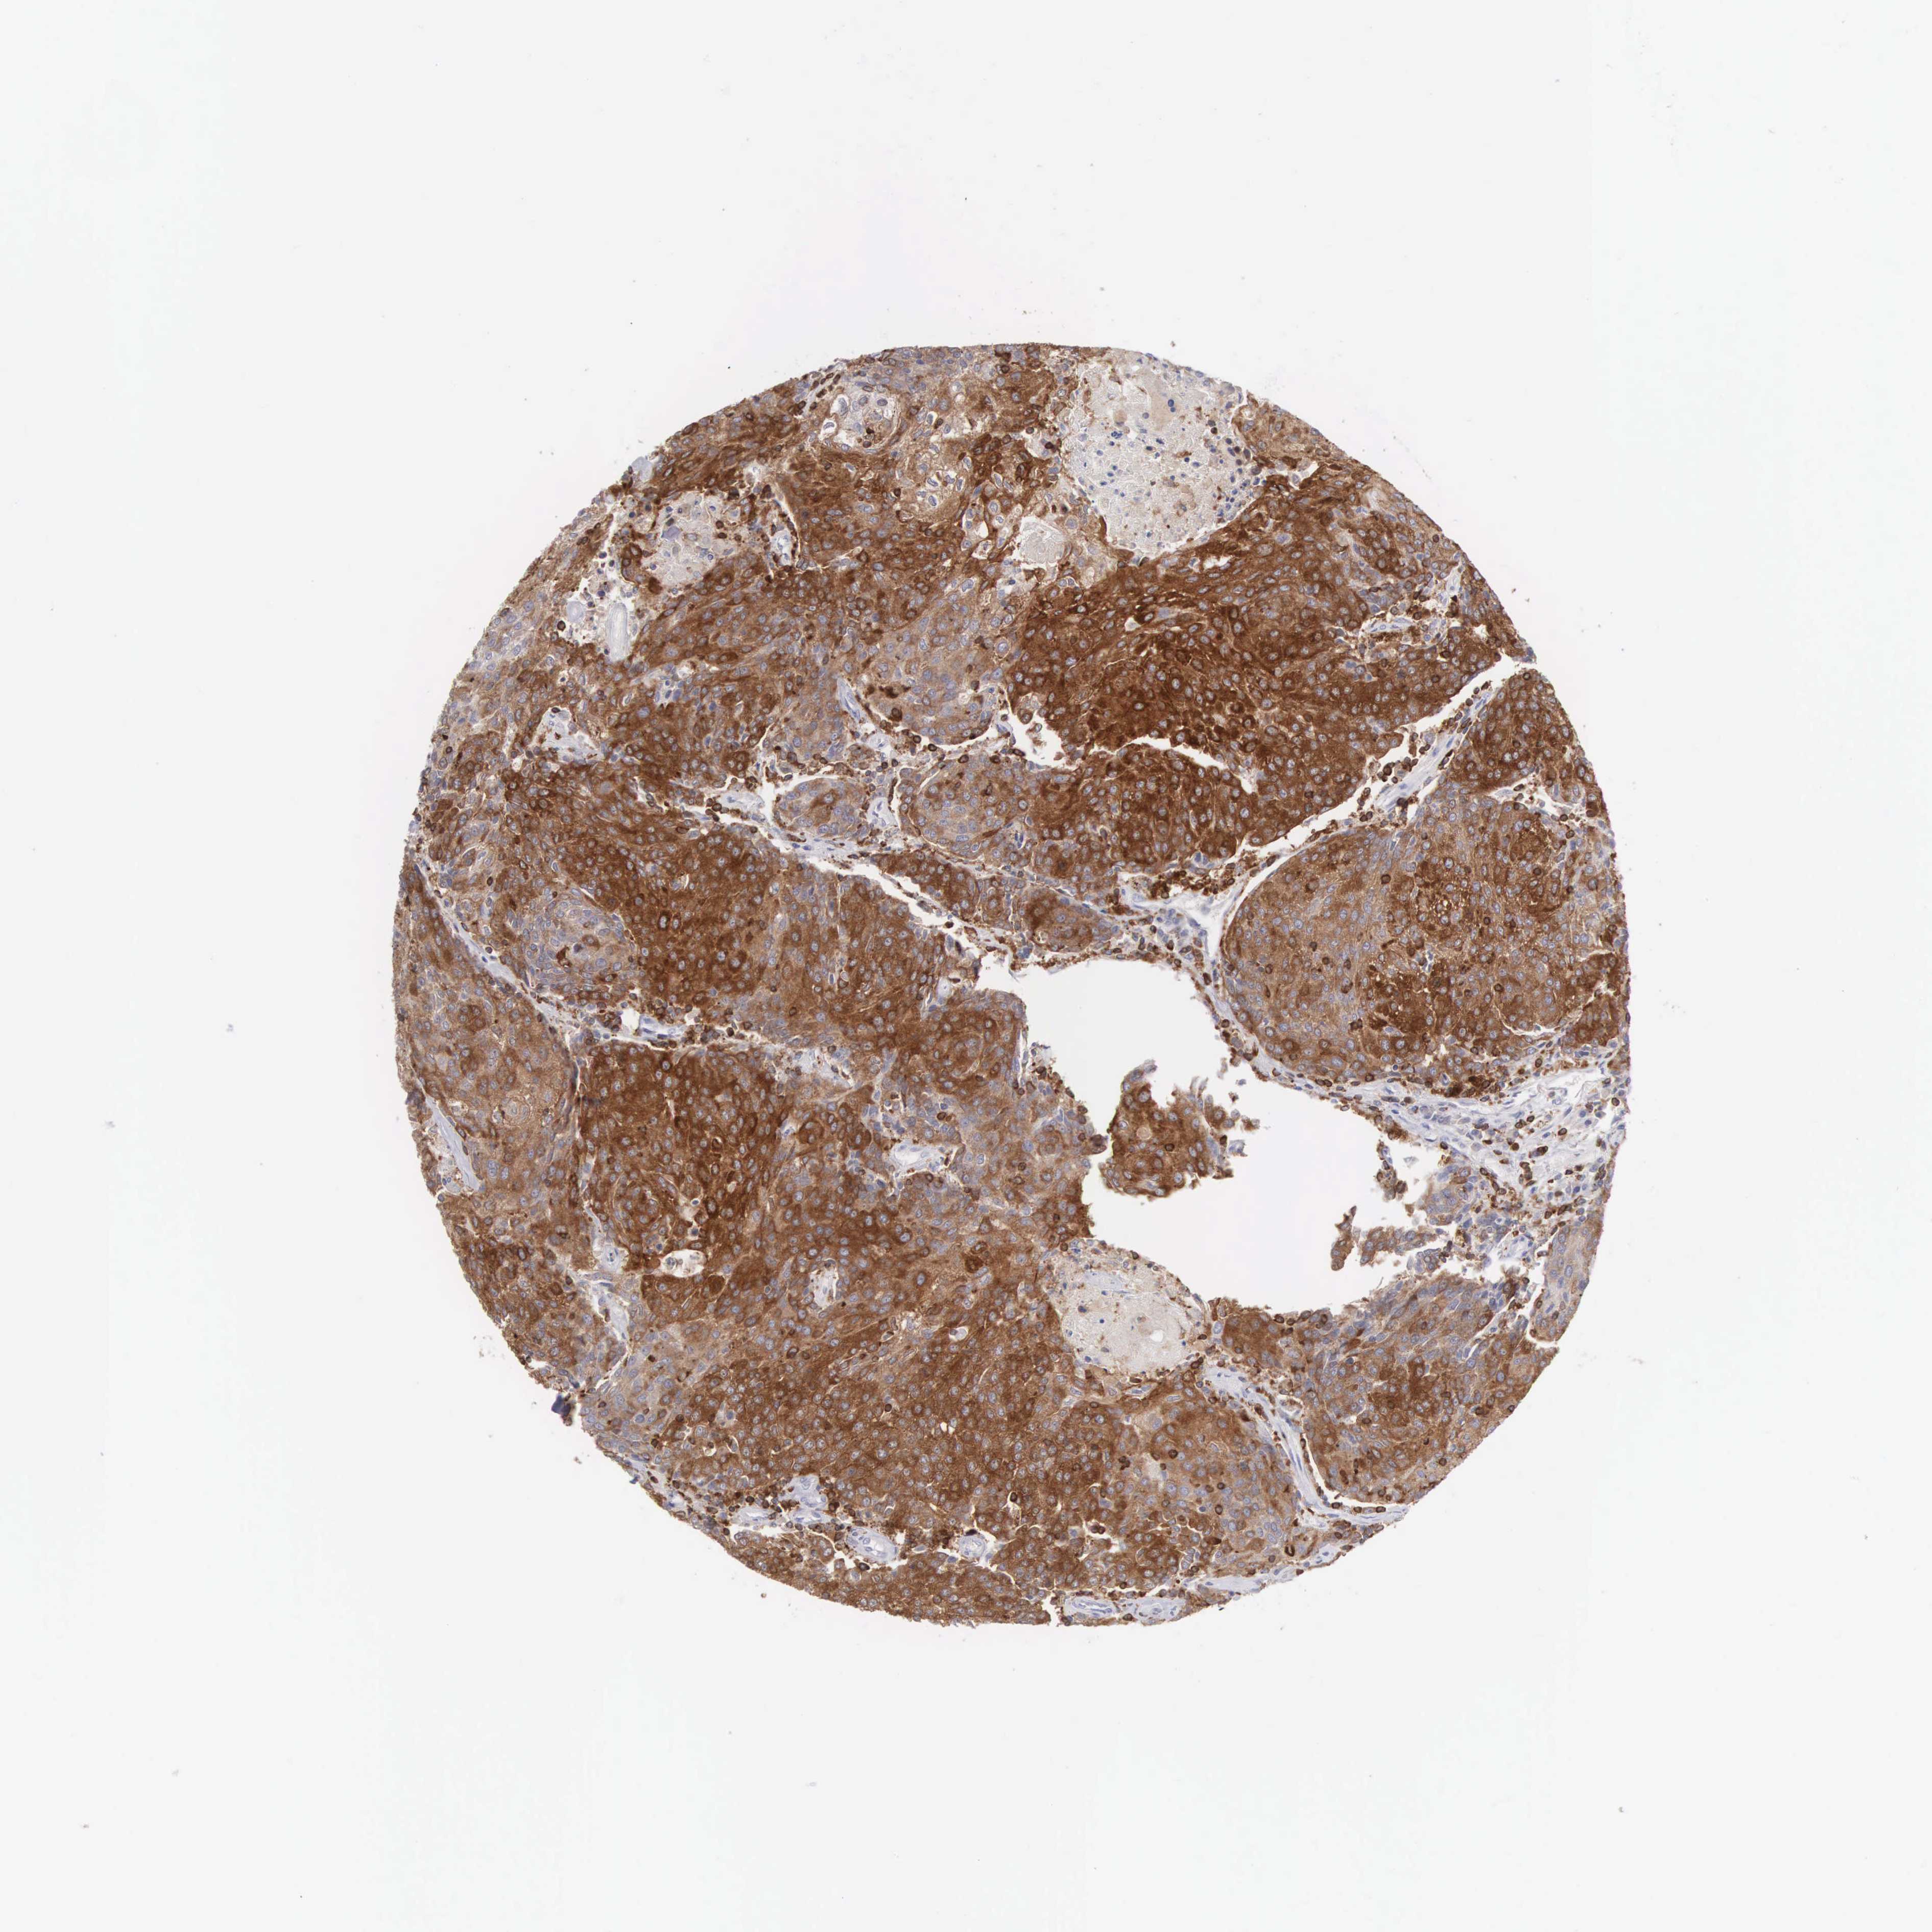

UROTHELIAL CANCER - Protein expressioni

A mouse-over function shows sample information and annotation data. Click on an image to view it in a full screen mode. Samples can be filtered based on level of antibody staining by selecting one or several of the following categories: high, medium, low and not detected. The assay and annotation is described here.

Note that samples used for immunohistochemistry by the Human Protein Atlas do not correspond to samples in the TCGA dataset.

Antibody stainingi

Antibody staining in the annotated cell types in the current human tissue is reported as not detected, low, medium, or high, based on conventional immunohistochemistry profiling in selected tissues. This score is based on the combination of the staining intensity and fraction of stained cells.

Each image is clickable and will lead to virtual microscopy that enables deeper exploration of all samples and also displays staining intensity scores, fraction scores and subcellular localization as well as patient and tissue information for each sample.

Antibody HPA000757

Staining

High

Medium

Low

Not detected

Intensity

Strong

Moderate

Weak

Negative

Quantity

>75%

75%-25%

<25%

None

Location

Nuclear

Cytoplasmic/membranous

Cytoplasmic/membranous,nuclear

Urothelial carcinoma, High grade

Urothelial carcinoma, Low grade